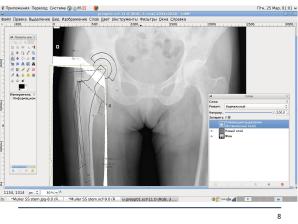

Сегодня свободное программное обеспечение имеет значительное количество зрелых графических пакетов, удовлетворяющих представленным требованиям. Мы в своей работе используем The GIMP ввиду его кроссплатформенности, возможности работы с DICOM-файлами и широкой распространённости.

Характер самого планирования практически не отличается от такового с использованием проприетарного ПО; специализированные шаблоны готовятся средствами того же The GIMP путём преобразования отсканированных файлов в векторные или пиксельные трансперентные.